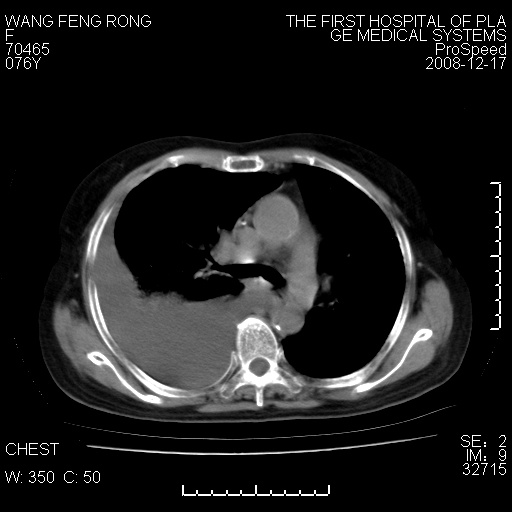

标题: CT17742:咳嗽,消瘦一月,有结果

右肺大部实变,其内可见支气管影,但分支减少,宽窄不均,走行僵直,同侧胸腔大量积液;纵隔内见多发淋巴结影,但淋巴结大部有钙化;主动脉壁钙化;临床上病人咳嗽、消瘦。所以我考虑:1、结核(依据:右下肺实变,纵隔内淋巴结符合结核表现,同侧并发胸膜炎表现);2、支气管肺泡癌(依据:实变的肺组织内支气管分支减少,宽窄不均,走行僵直,没有把它放在第一诊断是因为没有看到明显肿大的淋巴结);3、动脉硬化(主动脉壁钙化就支持这个诊断)。

病理结果,肺泡癌